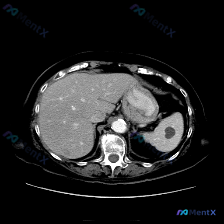

整理了一份很有意思的影像读片案例,一开始容易被提问带偏,仔细看下来其实是一个非常好的“临床思维”训练。 --- 病例基本情况 用户提出的问题是:“图像中描绘的具体异常是什么?脾脏病变”,附带了一幅腹部CT横断面(软组织窗)图像。 关键影像表现 我梳理了一下图像里的核心信息: 1. 脾脏:大小、形态正...

最近看到一个很有意思的影像分析场景,整理了一下思路和大家分享。 先看基础情况 用户预设了“脾脏病变”的方向,提供了一张腹部CT横断面软组织窗图像,从分析来看是增强扫描的动脉期或早期门脉期。 这张CT的核心表现 先整理一下明确的阳性/阴性信息: ✅ 图像质量:清晰度良好,无明显运动/金属伪影,软组织辨...

整理了一份很有意思的读片病例,差点被最初的提问带偏,分享一下思路: 病例背景 核心提问是“这张图里脾脏有什么病变?”,先来看影像的客观描述。 关键影像信息(增强CT横断面) 1. 扫描层面与质量:上腹部增强,对比度好,结构清。 2. 我们重点看的脾脏:边缘轮廓大致正常,未见明确局灶性低密度、高强化或...

今天看到一个挺有意思的影像分析场景:拿到一张上腹部CT横断面(软组织窗),问题直接指向“脾脏病变”,但仔细看完影像描述,我觉得这里可能藏着一个临床思维的小陷阱。先把资料理一理: --- 影像描述核心信息整理 肝脏:轮廓清晰,形态正常,肝实质密度均匀,未见明确局灶性占位,肝内血管走行自然。 脾脏:左上...

今天看到一份很有意思的腹部CT读片案例,整理一下思路和大家分享。 病例背景 用户最初的问题是「识别图中的脾脏病变」,但拿到图像(腹部CT横断面软组织窗)后,先按流程做了系统评估。 --- 影像关键信息整理 先把看到的客观情况列出来: 1. 脾脏:形态大小正常,包膜光滑,密度均匀,未见任何局灶性异常,...

最近看到一个读片资料,预设问题是“图像中是否存在脾脏病变”,先和大家理一下完整的思路。 --- 先列一下拿到的「影像客观事实」 这是一幅上腹部CT软组织窗横断面图像: 1. 肝脏:轮廓平整,实质密度均匀,肝内血管走行清晰,无受压移位; 2. 脾脏:划重点——形态正常、大小正常、实质密度均匀,未见局灶...

今天看到一个提问很有意思——直接问“脾脏病变”,但把影像资料和分析理了理,发现这里有个很典型的临床认知陷阱,整理出来和大家讨论。 先把完整客观影像信息放前面(别被提问带偏): --- 一、客观影像所见(腹部CT平扫软组织窗) 1. 图像质量:伪影少,软组织对比度好,满足诊断 2. 关键解剖结构: -...